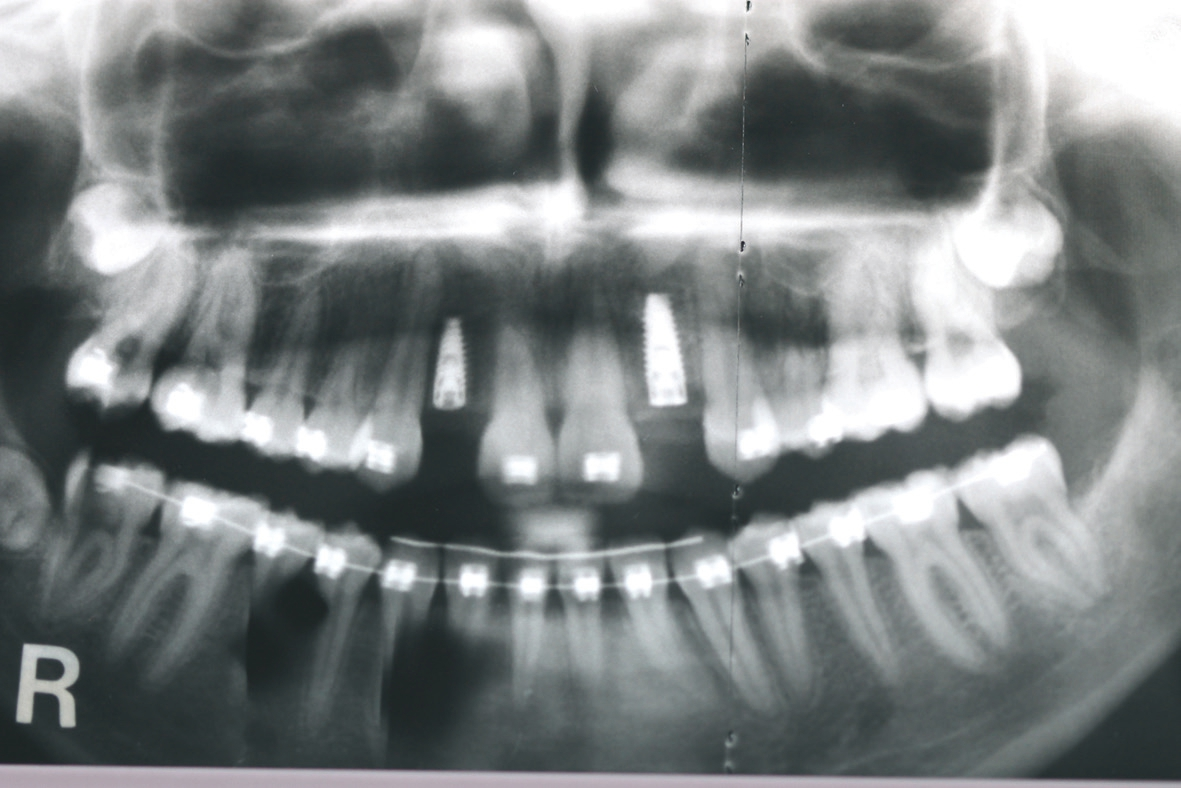

Nach viereinhalbmonatiger Einheilung der allogenen Knochenblöcke wurde wiederum ein Mukoperiostlappen mit einseitigem vertikalen Entlastungsschnitt gebildet und die Implantate prothetisch nach korrekter prothetischer Planung mit Hilfe einer Schablone in regio 12 und 22 inseriert (Abb. 9 und 10). Zur erneuten Auskonturierung wurden allogene Knochenspäne bukkal unter den Mukoperiostlappen geschoben und zur Weichgewebsaugmentation eine erneute autologe L-PRF-Membran nach Choukroun appliziert (Abb. 11 und 12). Abbildung 13 zeigt das postoperative OPG nach Insertion der beiden Implantate. Zur provisorischen Versorgung erhielt die Patientin wiederum beidseitig eine palatinal verklebte Maryland-Brücke regio 12 und 22.